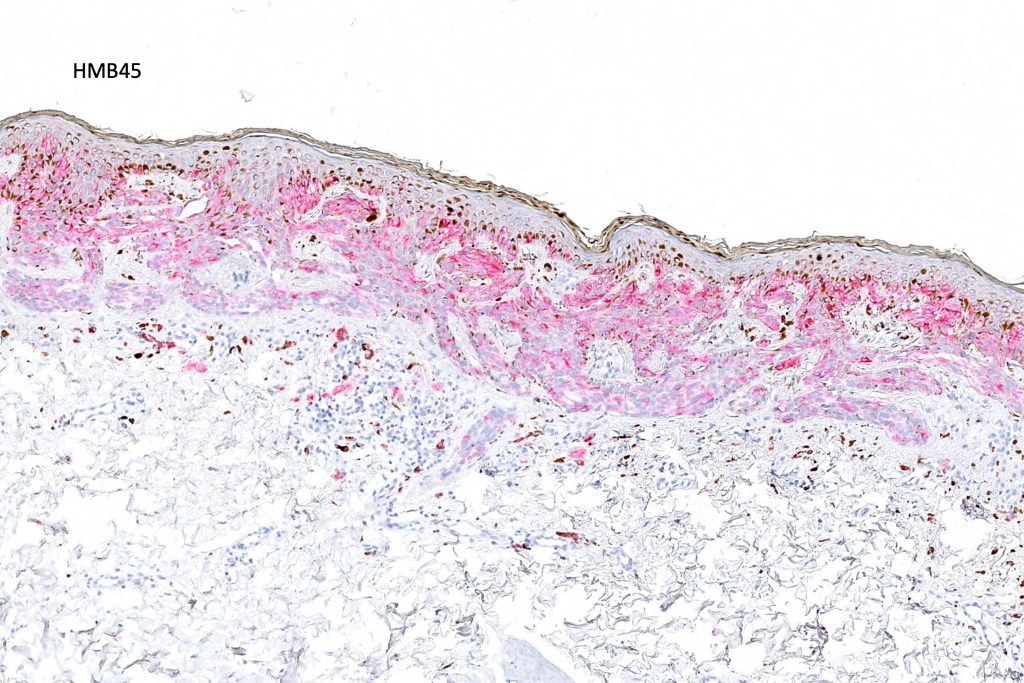

•80 % kinase fusions (NTRK3-58%), HMB45 diminishes with depth in compound lesions